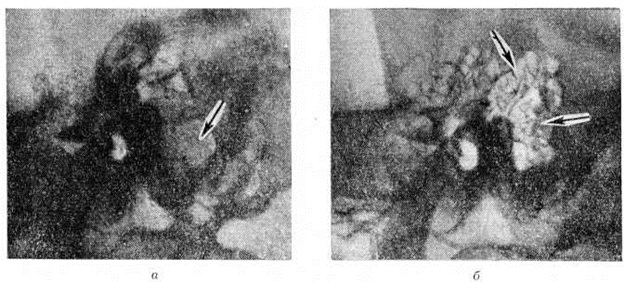

Рис. 5.

Рентгенограммы височной кости больного с верхушечным мастоидитом: а — височная кость в боковой проекции — ячейки сосцевидного отростка резко затемнены, б — сосцевидный отросток в косой проекции — стрелкой указан полный дефект кортикальной пластинки отростка.

Крупная одиночная ячейка в сосцевидном отростке (относительно редкий анатомический вариант), дающая в норме на рентгенограмме интенсивное просветление, может быть принята за Мастоидит с субпериостальным абсцессом (рисунок 4). Отличить полость субпериостального абсцесса от полости, вызванной холестеатомой в сосцевидном отростке, можно по характеру их границ. Полость субпериостального абсцесса, как правило, не имеет чётких очертаний, свойственных холестеатоме (смотри полный свод знаний). В сомнительных случаях диагностика проводится только путём клинико-рентгенологическое сопоставлений. Верхушечный Мастоидит (абсцесс Бецольда) может быть легко пропущен, если сделать одну боковую рентгенограмму височной кости (рисунок 5, а). При толстой наружной пластинке коркового вещества сосцевидного отростка костный дефект внутренней пластинки на боковом снимке не обнаруживается. На снимке в косой проекции по Стенверсу дефект этой пластинки выявляется чётко (рисунок 5, б). Для распознавания верхушечного Мастоидит очень важен учёт клинические, симптомов, определяющих тактику рентгенолога. Симптом полости рентгенологически нередко обнаруживается и при замаскированных Мастоидит при лечении антибиотиками. Рентгенологические наблюдение показывает, что консервативное лечение Мастоидит при благоприятных исходах ведёт к полной костной регенерации полости абсцесса и восстановлению воздушности сохранившихся ячеек. Серийное послойное рентгенологическое исследование височной кости таких больных указывает на замещение дефекта нормальной костной тканью (рисунок 6, а, б) и перестройку сосцевидного отростка, тип строения которого из распространённого пневматического становится смешанным спонгиозно-пневматическим. Рентгенологические наблюдения указывают на длительность этого процесса (1 — 2 года).